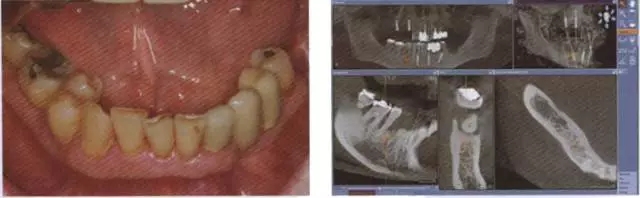

圖8 牙周病破壞了下合的牙齒系統(tǒng)

圖9 對(duì)牙周病破壞的下合員牙齒通過(guò) CBCT數(shù)據(jù)進(jìn)行帶角度的種植規(guī)劃.